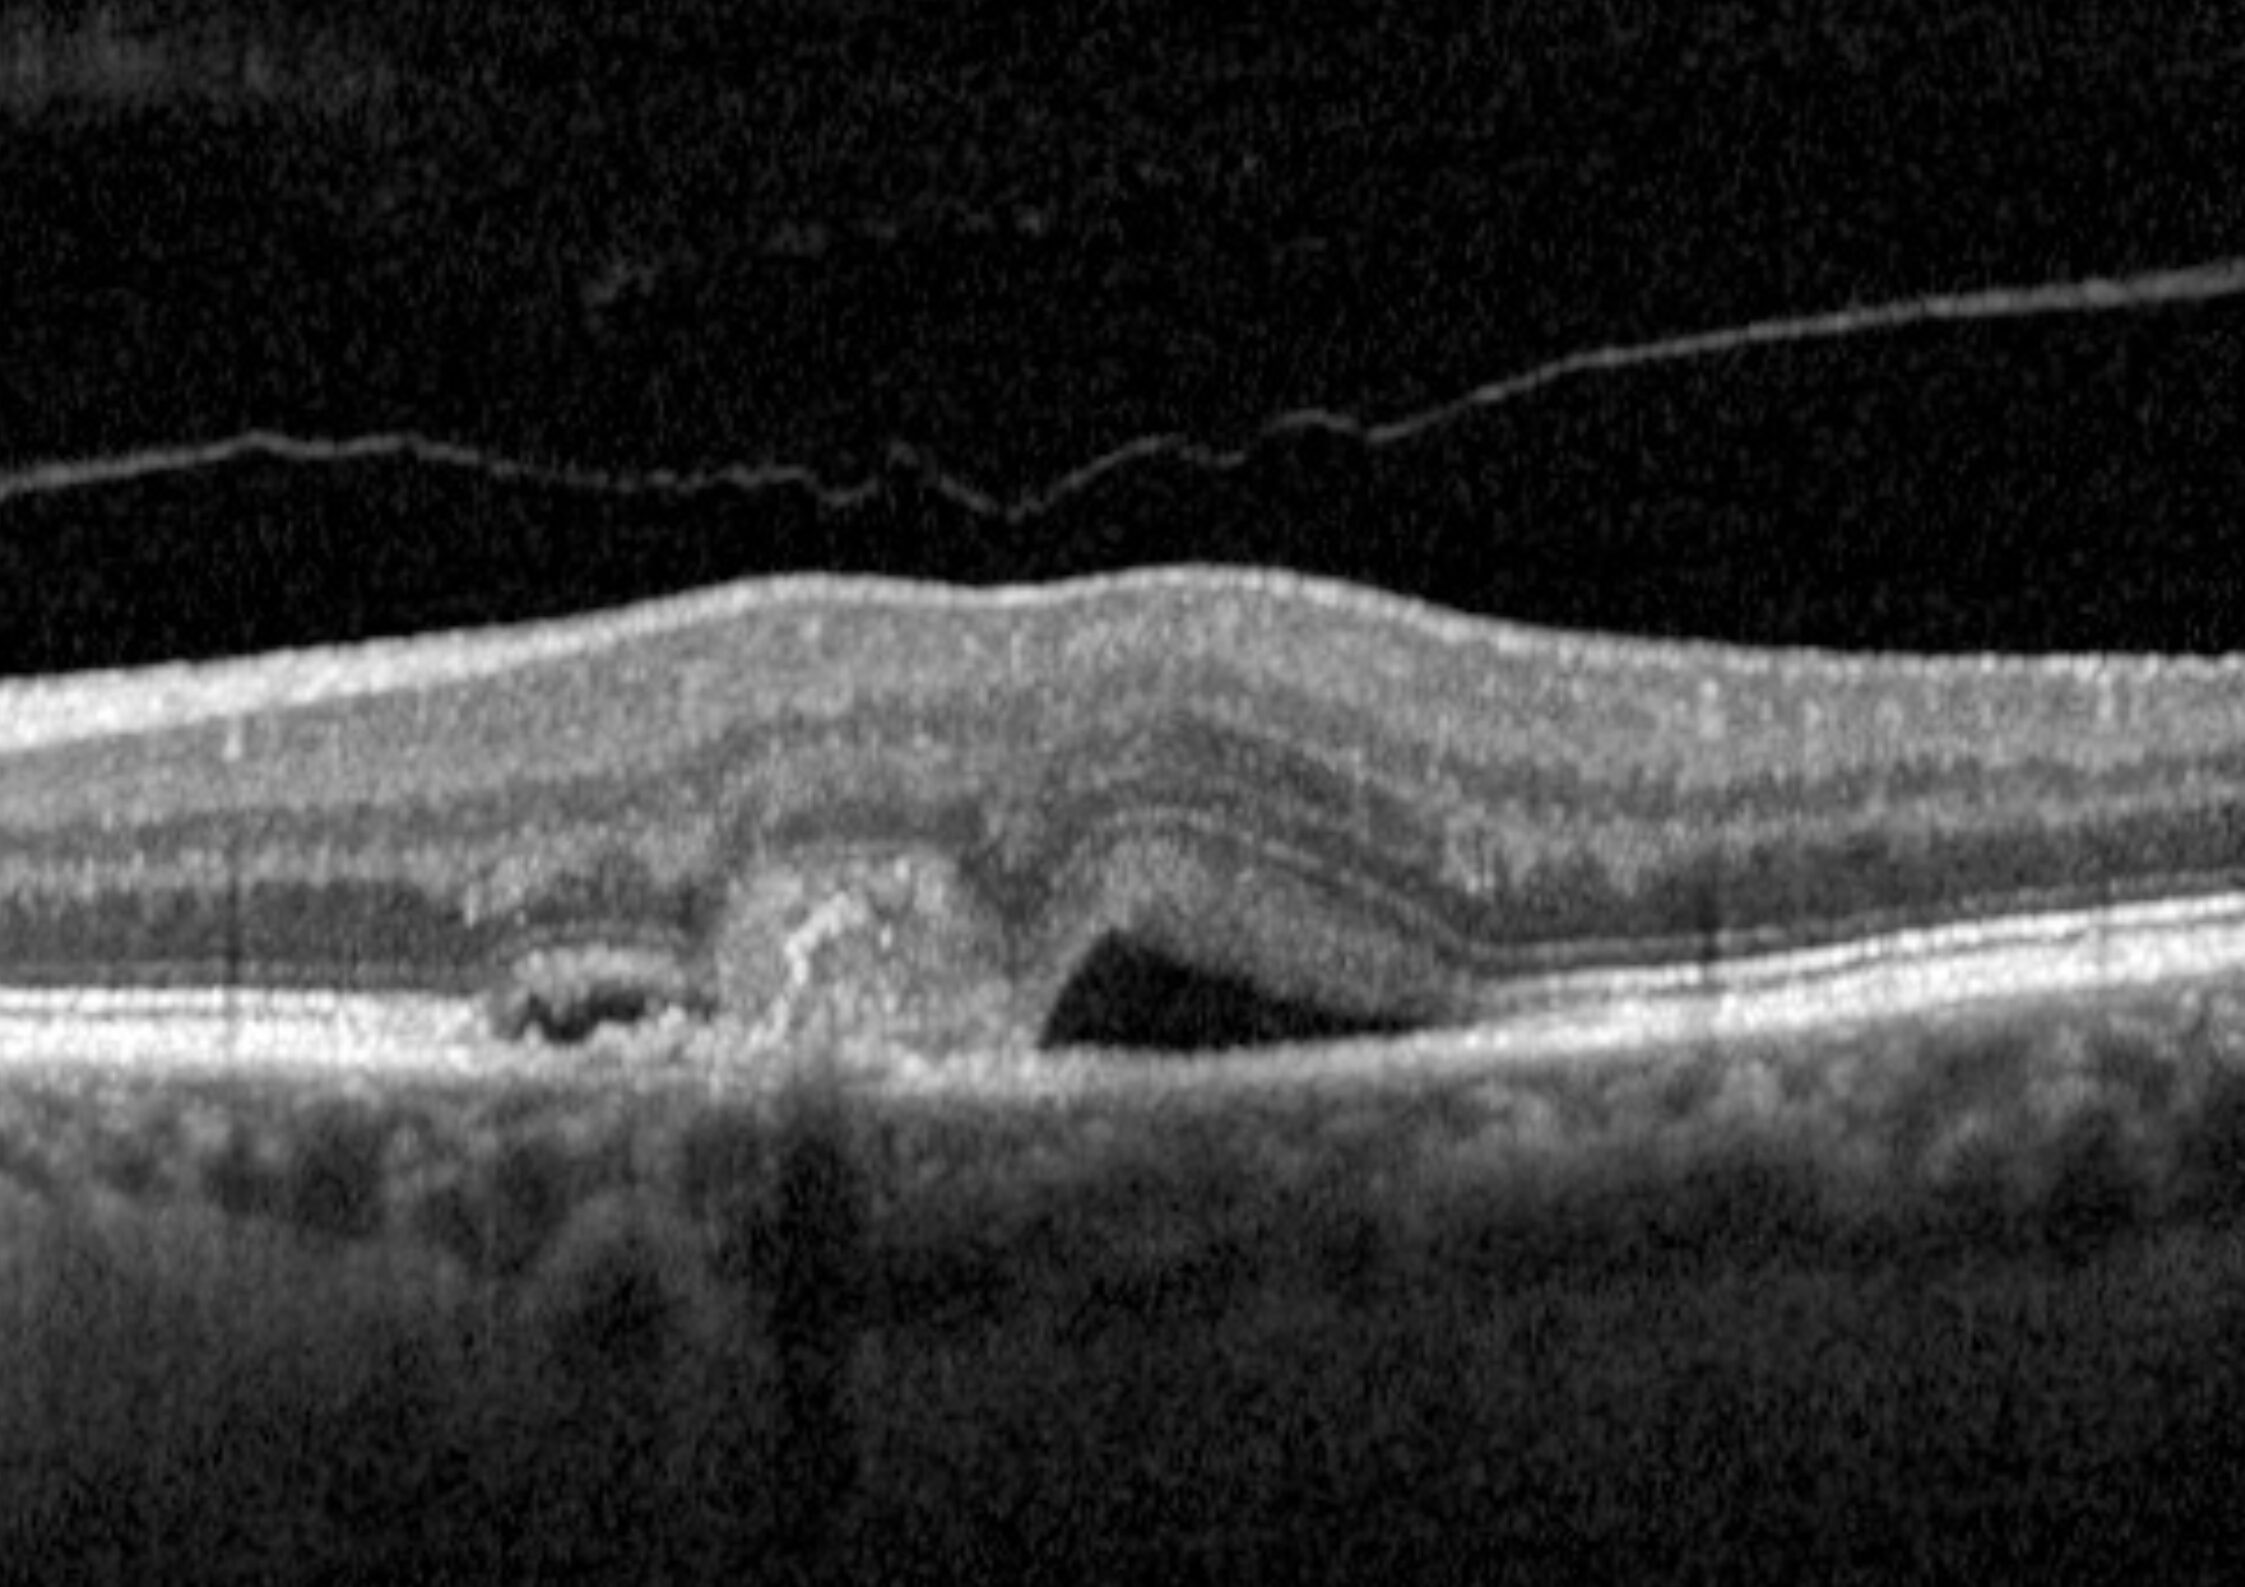

- Maculopatia essudativa

- Edema maculare diabetico

- Occlusioni venose retiniche

Questi farmaci rappresentano l’unica terapia al momento esistente per il trattamento della maculopatia essudativa e dell’edema maculare. I principali effetti dell’inibizione del VEGF sono:

- Regressione dei neovasi patologici

- Riduzione dell’edema retinico